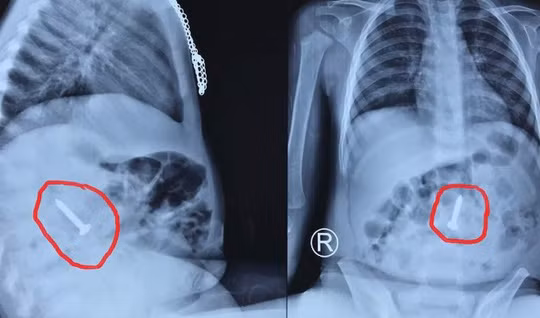

| Đinh vít nằm trong tá tràng cháu bé. Ảnh: BV cung cấp |